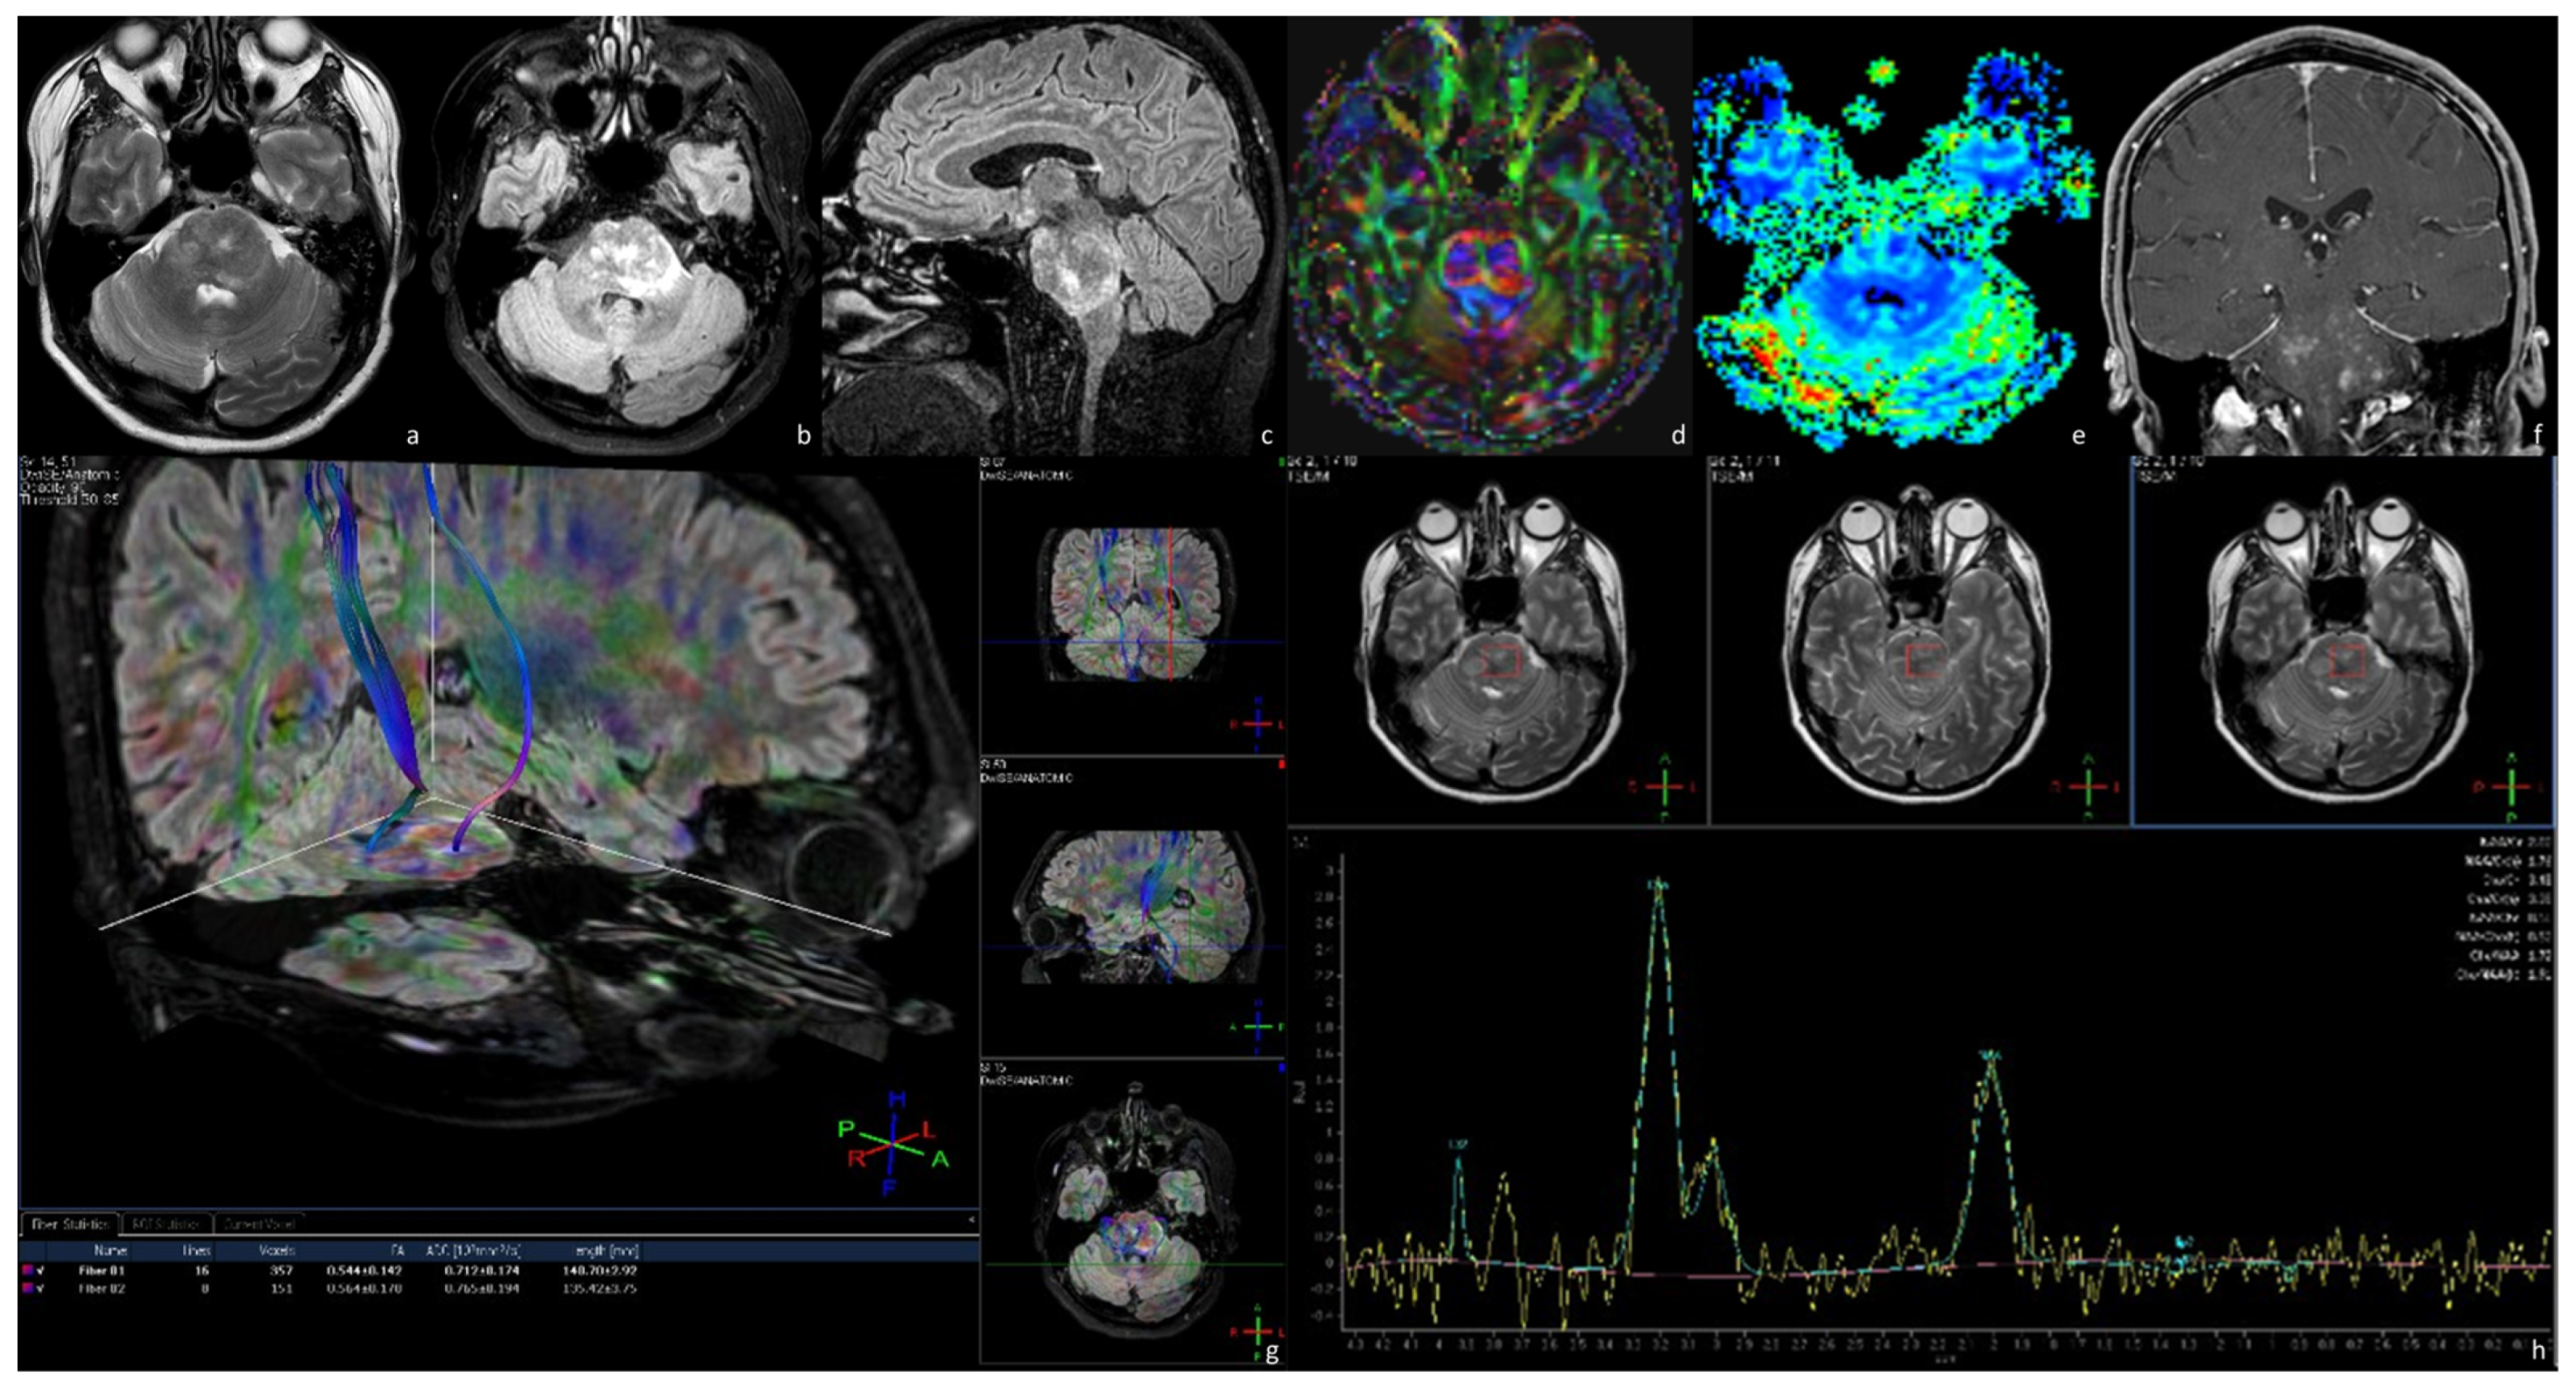

3.4.1. Exophytic Brainstem Gliomas (EBSGs)